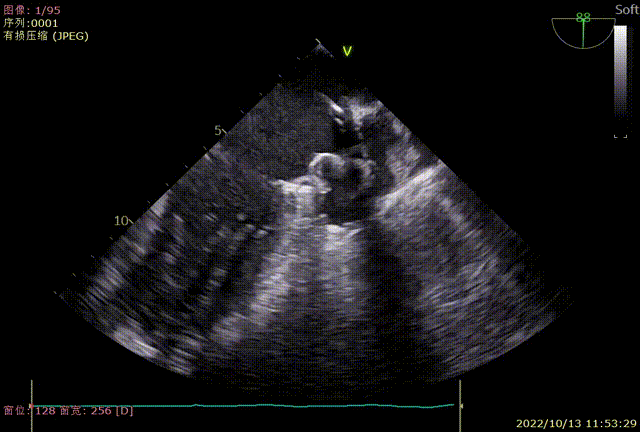

术中TEE各角度检查左心耳

TEE0度封堵效果

TEE45度封堵效果

TEE90度封堵效果

TEE135度封堵效果